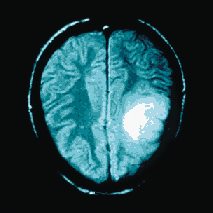

La démence de type Alzheimer est la forme de démence la plus répandue. Elle a été décrite en 1907 comme une affection associant une démence progressive à des lésions histologiques particulières du cerveau. On estime qu'au moins 5 % des personnes âgées de plus de 65 ans souffrent de démence accompagnée de troubles progressifs de la mémoire, du comportement et des fonctions cognitives. Le début de cette maladie est lent et insidieux, marqué le plus souvent par des troubles de la mémoire. D'autres signes sont importants : troubles du langage et de la gnosie (connaissances acquises de l'environnement par perception sensorielle), apraxie (coordination anormale des mouvements vers un but proposé), troubles du comportement (émoussement affectif, réactions anxio-dépressives, irritabilité, hallucinations visuelles et auditives…) et perte de l'autonomie…

Il est établi que certaines cellules du cerveau libérant de l'acétylcholine dégénèrent de manière sélective dans la démence de type Alzheimer. La maladie se caractérise par la présence d'enchevêtrements de neurofibrillaires et de plaques séniles dans le cerveau. Ces deux phénomènes sont associés à une perte neuronale. Les plaques séniles sont généralement constituées par des dépôts de protéines. Les protéines forment la charpente des tissus nerveux, au sein de la névralgie (astrocytes, oligodendrocytes) dans laquelle s'organisent les neurones et leurs synapses.

La synthèse des protéines est essentielle à la qualité structurale et fonctionnelle des cellules nerveuses ; leur vieillissement prématuré, avec dénaturation et précipitation, constitue les dépôts amyloïdes que l'on retrouve dans les plaques séniles de la démence de type Alzheimer. Cette dénaturation semble induite par un processus oxydant qui, par la création d'un excès de radicaux libres, altère les liaisons peptidiques et les liaisons intermoléculaires des polyaminoacides.